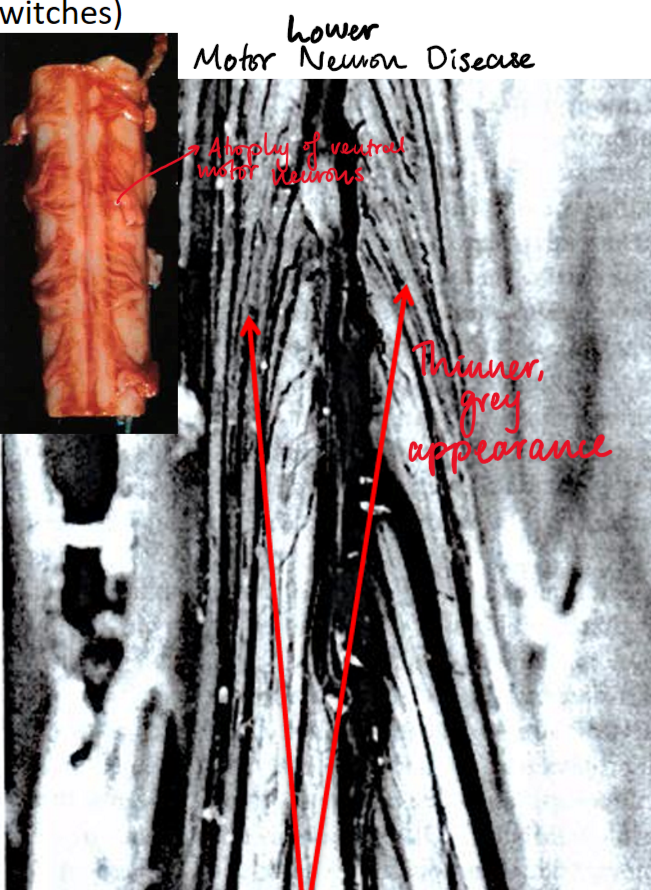

Amyotrophic lateral sclerosis (ALS)

(definiton + pathogenesis + signs + clinical progression)

Progressive neurological disorder causing selective degeneration of motor neurons responsible for voluntary muscle activity

Pathogenesis:

Poorly understood, related to superoxide dimutase (SOD1) mutations on chromosome 21 causing neural inclusions and cytotoxicity

LMN disease: atrophy of ventral spinal nerve roots causing skeletal muscle denervation

UMN Disease: degeneration of corticospinal tracts in lateral portion of SC

Signs:

LMN disease: weakness, fasciculations

UMN disease: paresis, hyperreflexia, spasticity, +ve babinski sign